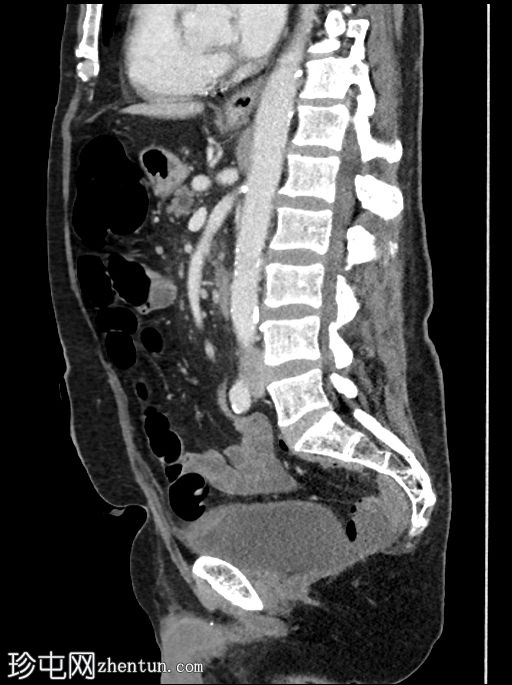

轴位增强扫描(门静脉期)

1.jpg

可见胆道支架位置良好,管腔内可见分层气液平面。支架远端位于充满液体的D2段内。支架内未见明显放射性结石。

肝内胆管未扩张,但可见胆道积气。

胰头水肿,伴胰周脂肪浸润。未见明显积液。

胰头局灶性结节(代表已知的肿瘤),伴有上游主胰管扩张,位于萎缩的胰颈、胰体和胰尾内。背景可见胰腺实质内钙化。